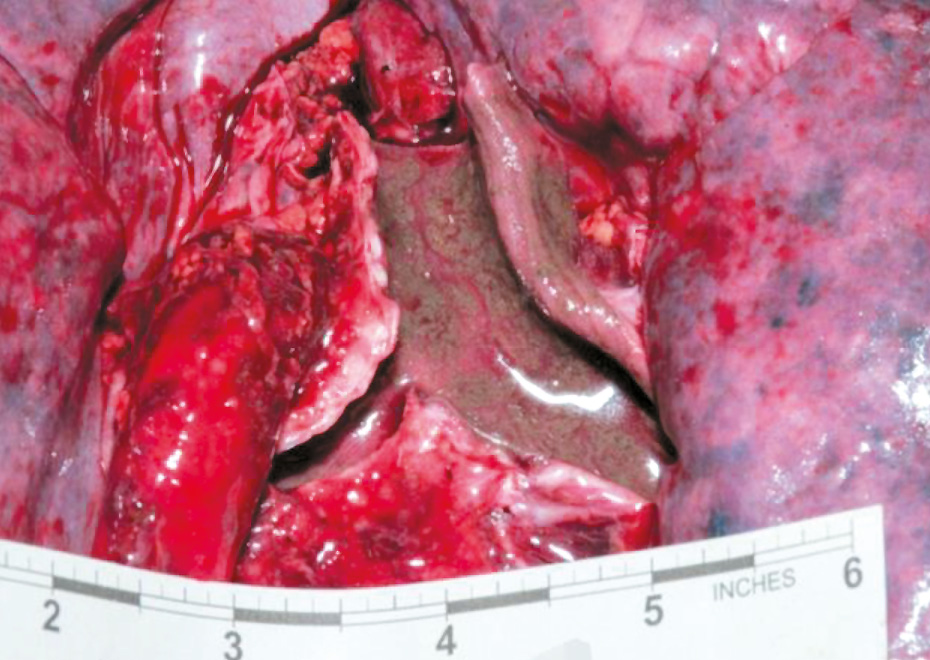

Emphysema aquosum is frequently highlighted in forensic literature as an important drowning sign, and accompanying lung changes must be correctly interpreted [15]. As a result of the airways closing during expiration, increased phlegm production and foam creation cause the hyperinflated lung as a valve mechanism. These mechanisms create the image of ballooned lungs filling the pleural cavities and reaching over the pericardium with their edges (Fig. 5). Imprints of the ribs on the lung surface can often be seen. Histologically, the overinflated lungs present flattened and ruptured interalveolar septa surrounding blister alveolar cavities. In addition, anemic and normally perfused areas alternate in the lungs, whereas the alveoli–capillary membrane is damaged. The severity of this injury is proportional to the duration of the drowning process. Other signs of pulmonary hyperinflation include washed-out rhexis bleeding under the pleura, called Paltauf’s spot [15]. Paltauf’s spot refers to bleeding spots caused by increased pressure, leading to the rupture of the alveolar walls, mostly found on the anterior surfaces and borders of the lung, and can be found in the subpleural if there has been further leakage or rupture [7].

Fig. 5. Emphysema aquosum and intra-alveolar edema [8].